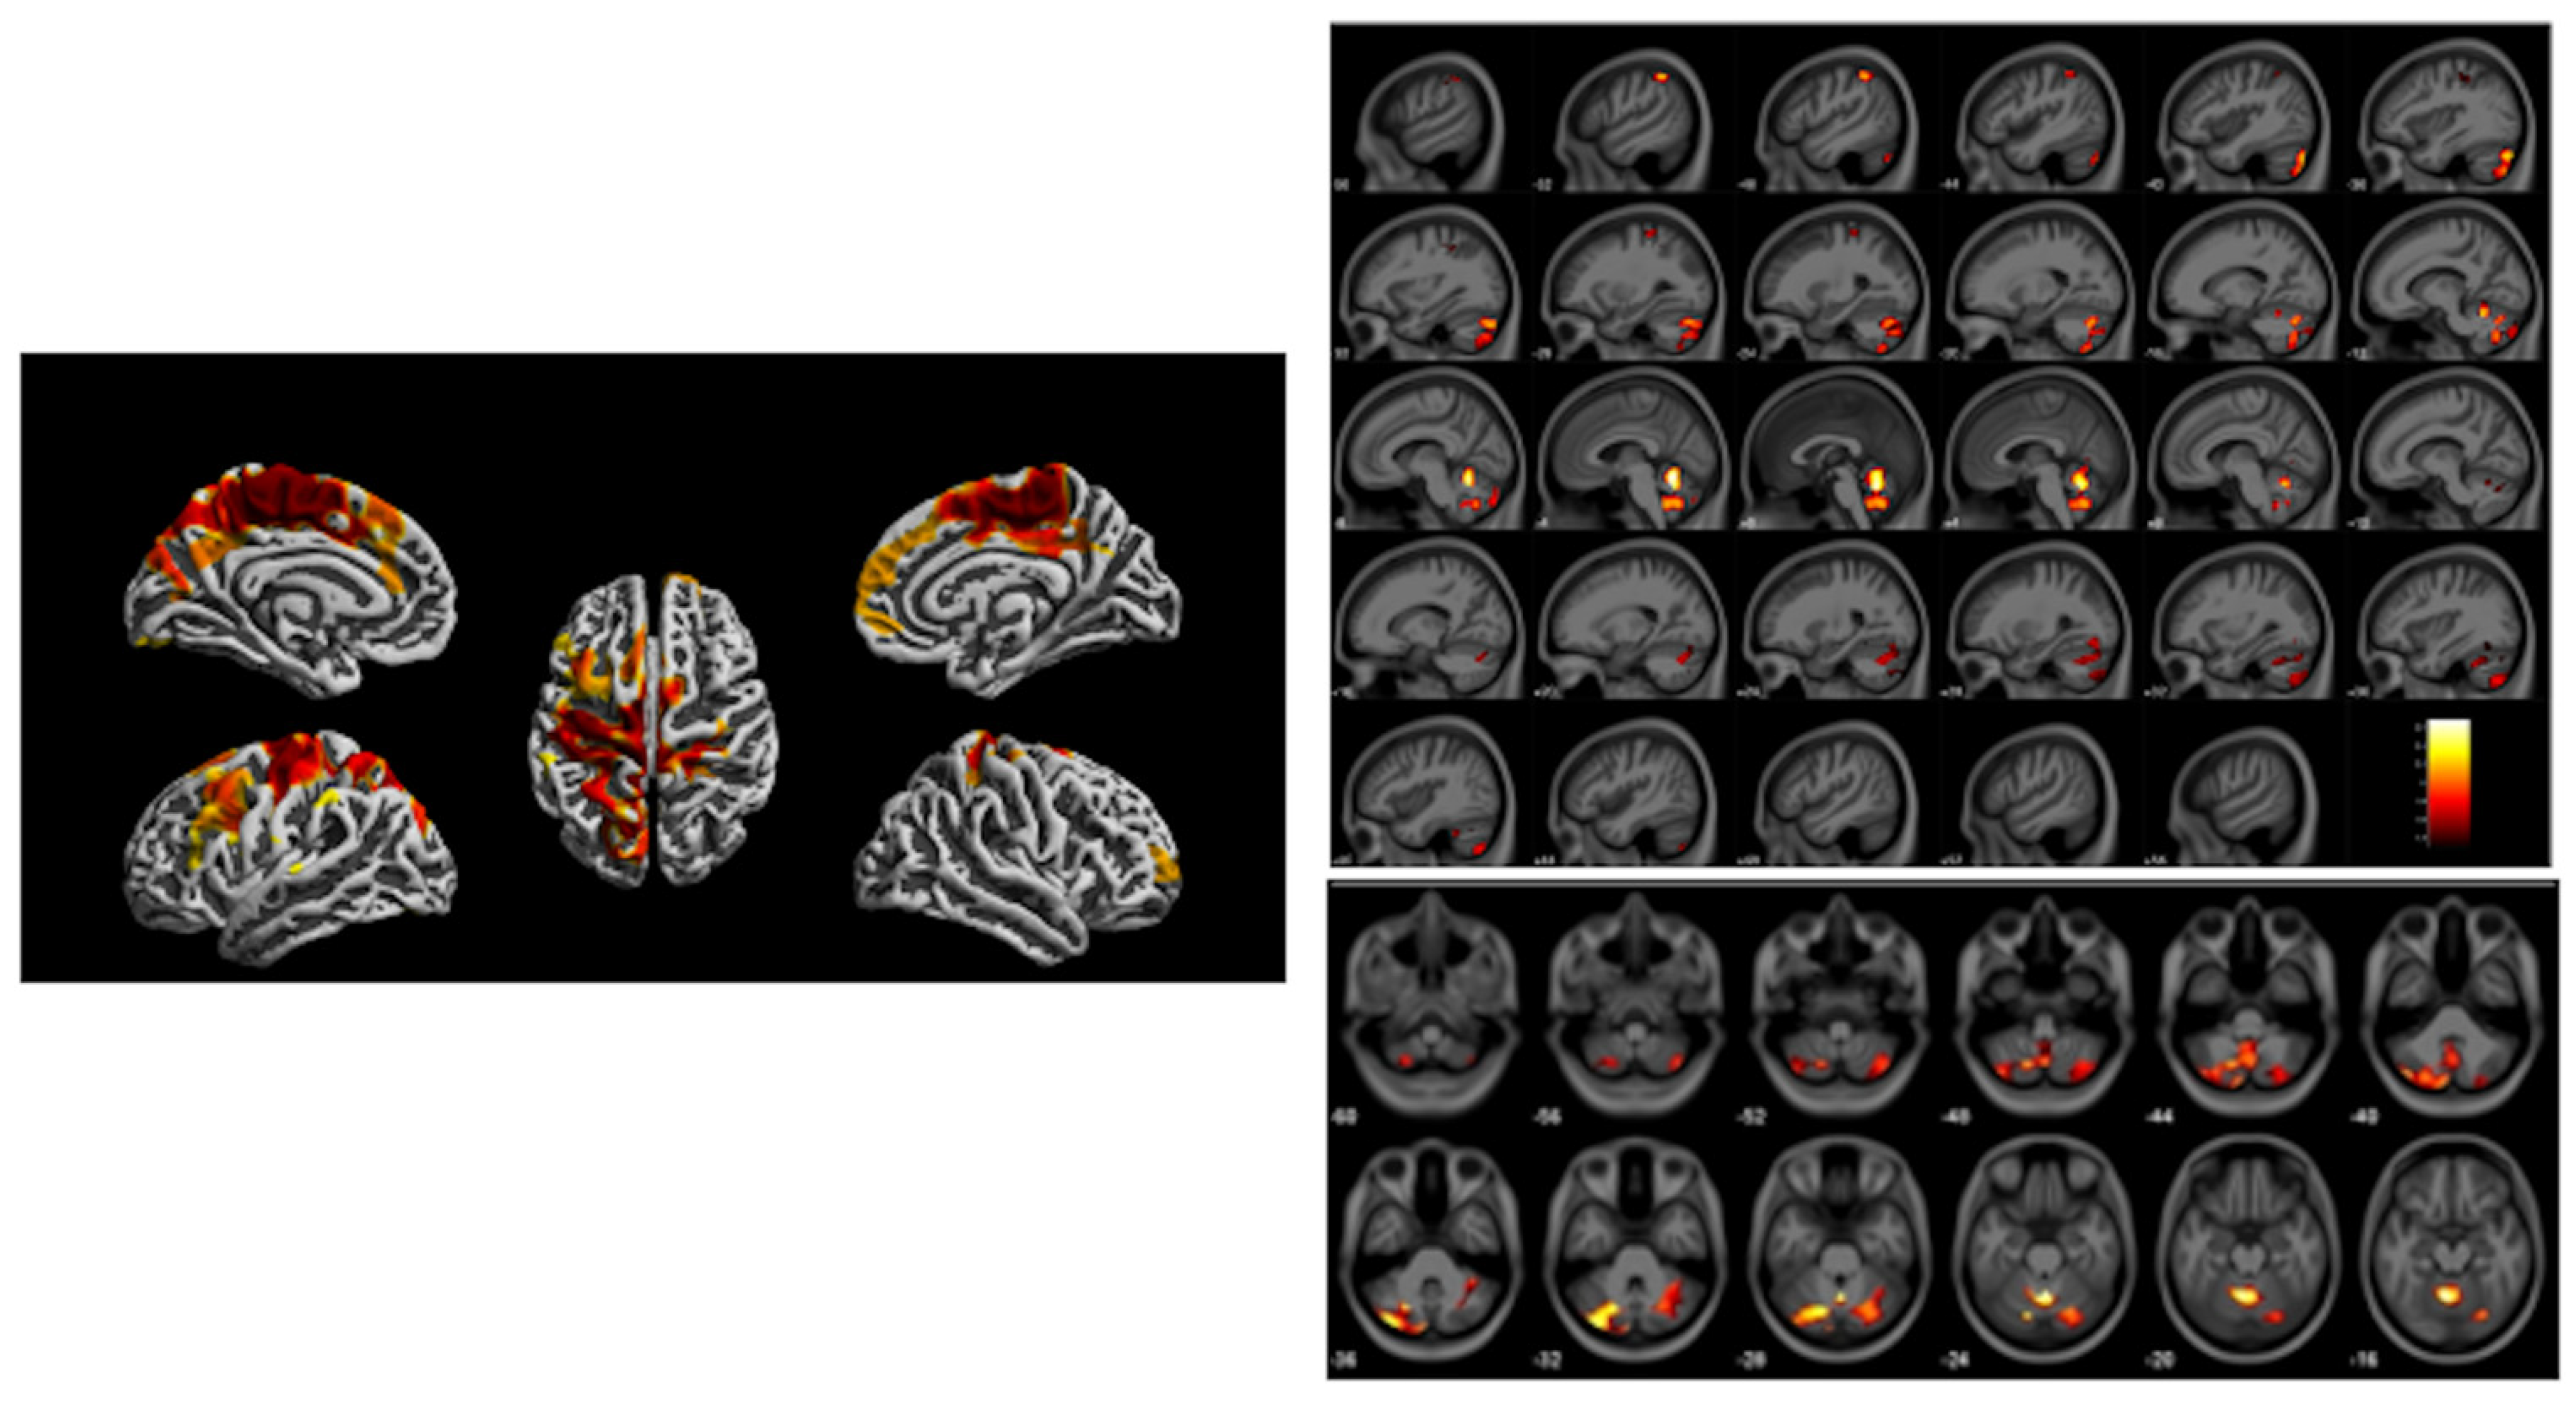

- Cecil, K.M.; Brubaker, C.J.; Adler, C.M.; Dietrich, K.N.; Altaye, M.; Egelhoff, J.C.; Wessel, S.; Elangovan, I.; Hornung, R.; Jarvis, K.; et al. Decreased brain volume in adults with childhood lead exposure. PLoS Med. 2008, 5, e112. [Google Scholar] [CrossRef]

| Childhood Blood | MRI: SPM, VBM [6] | Adult | Reduced frontal cortex and white matter volumes | Cecil et al. [7] |

| Childhood Blood | MRI: SPM, VBM [6] | Adult | Reduced frontal cortex and white matter volumes | Beckwith et al. [8,9] |